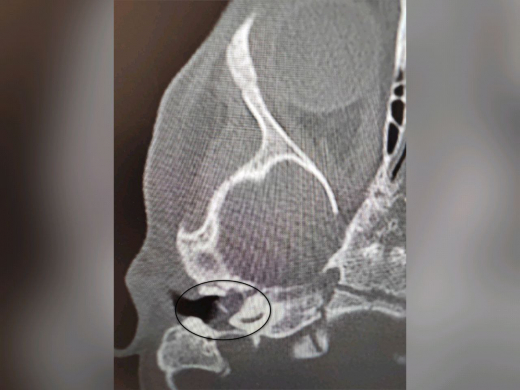

Специалисты ВОКБ №1 провели уникальную операцию двухлетней пациентке с редкой патологией – врожденной холестеатомой. Врачам удалось не только удалить опасное образование, но и полностью сохранить слух ребенка. Об этом сообщает пресс-служба облздрава в среду, 5 ноября. Поводом для обращения в больницу стали жалобы на боли в ухе у девочки, которые появились после перенесенной ОРВИ. Стандартное лечение не помогало, а состояние осложнилось парезом лицевого нерва – у ребенка появилась слабость мимических мышц. Обследование выявило серьезный диагноз. – Врожденная холестеатома – кистозное образование в среднем ухе – редко встречается у детей так рано. Обычно ее диагностируют в 5-8 лет. Она опасна тем, что вызывает хроническое гноетечение и разрушает структуры, отвечающие за слух, – пояснили в медучреждении. Операцию проводил заведующий оториноларингологическим отделением Антон Мащенко. Под микроскопом он удалил холестеатому, провел декомпрессию лицевого нерва и восстановил механизм звукопроведения. – Хирургическое вмешательство позволило устранить образование, восстановить функцию нерва и, что крайне важно, сохранить слух, – отметили в больнице. Послеоперационный период прошел без осложнений, парез лицевого нерва удалось купировать. Уже на пятые сутки девочку выписали домой.